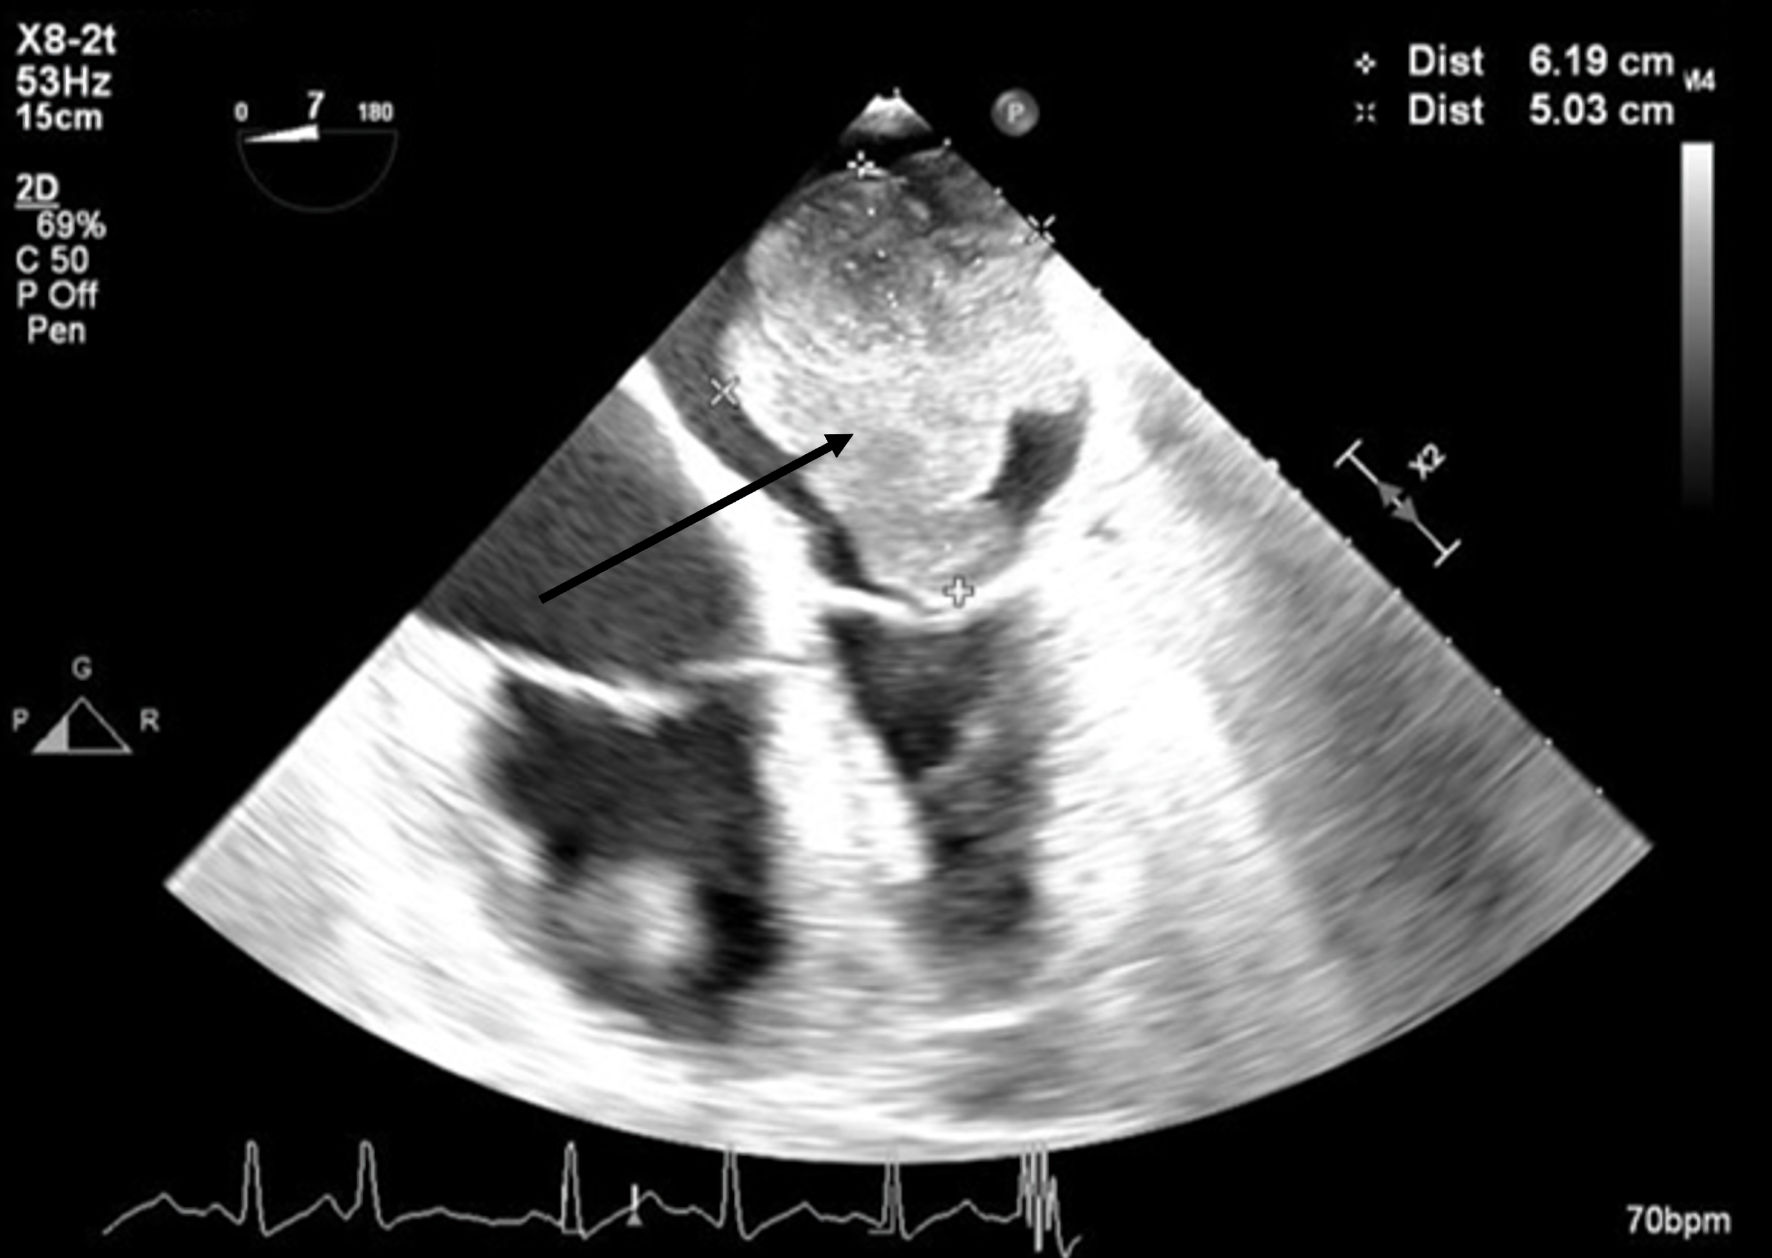

A 66-year-old obese woman presented to the emergency department (ED) with a 2-month history of progressive fatigue, 20-lb weight loss, orthopnea, wheezing, chest pressure, lower extremity edema, dyspnea on exertion, and paroxysmal nocturnal dyspnea. On examination, she had a systolic murmur. Transthoracic echocardiography (TTE) revealed a 5-cm mass occupying her left atrium. Right and left heart catheterization showed no flow-limiting coronary artery disease. Right heart pressures were as follows: right atrium 3 mm Hg, right ventricle 66/4 mm Hg, pulmonary artery 67/25 mm Hg, pulmonary capillary wedge pressure 25 mm Hg, and left ventricle 103/9 mm Hg. With plan for further workup, she was discharged and scheduled for elective resection. She returned to the ED 5 days later with severe acute hypoxic respiratory failure. On admission, vitals were as follows: heart rate (HR) 129, respiratory rate (RR) 44, SpO2 92%, and blood pressure (BP) 110/70. Her hypoxemia was managed with high-flow nasal cannula, and she was scheduled for urgent resection of her left atrial mass. In the operating room, she was severely orthopneic when the head of her bed was lowered below 90°. A radial arterial and internal jugular central venous catheter were placed while she was in a seated position on high-flow nasal cannula (fraction of inspired oxygen (FiO2) 100%, 35 liters per minute (LPM)). Femoral central venous and arterial cannulas were also placed prior to induction of anesthesia to enable emergent transition cardiopulmonary bypass (CPB). A dexmedetomidine infusion was used to facilitate vascular cannulation, surgical preparation, and draping. Vasopressin, epinephrine, and norepinephrine infusions were started preemptively, and she received a 250-mL albumin bolus. Her airway was secured with video laryngoscopy after induction with etomidate and rocuronium. After induction, she became profoundly hypotensive and hypoxemic, with mean arterial pressure (MAP) dropping by 30 mm Hg and oxygen saturation dropping to 70%. This brief episode resolved with administration of crystalloid, vasopressin boluses, and Trendelenburg positioning. Despite a transient period of hypotension and hypoxia, emergency CPB was not required. A median sternotomy was performed, and she was transitioned to CPB by aorto-bicaval cannulation. Intraoperative transesophageal echocardiography (TEE, X8-2t, EPIQ CVx; Philips Ultrasound, Bothell, WA) redemonstrated a large pedunculated mass traversing the interatrial septum and occupying the right and left atria. Mid-esophageal views were used to image the large heterogeneous mass (Figs. 1, 2). She was found to have a 7 × 4.5 cm left atrial mass arising from the lateral wall of the atrium near the left inferior pulmonary vein. Pulmonary venous return was obstructed, likely contributing to her pulmonary hypertension, pulmonary edema, and hypoxemia. During atrial systole, the mass traversed the mitral valve orifice and obstructed mitral inflow and the left ventricular outflow tract (LVOT). LVOT obstruction persisted during early ventricular systole, and flow acceleration was observed with color flow doppler (Figs. 3-5).

Figure 2. Mid-esophageal four-chamber view. A mass occupies the majority of the left atrium during systole. The arrow denotes the large cardiac tumor.

Figure 3. Mid-esophageal aortic long-axis view showing a mass obstructing the left ventricular outflow tract (LVOT) during early systole. The arrow indicates LVOT obstruction.